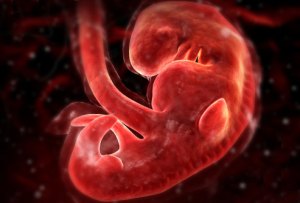

Fetus at 4 Weeks

All pictures came from:  http://www.webmd.com/baby/slideshow-fetal-development